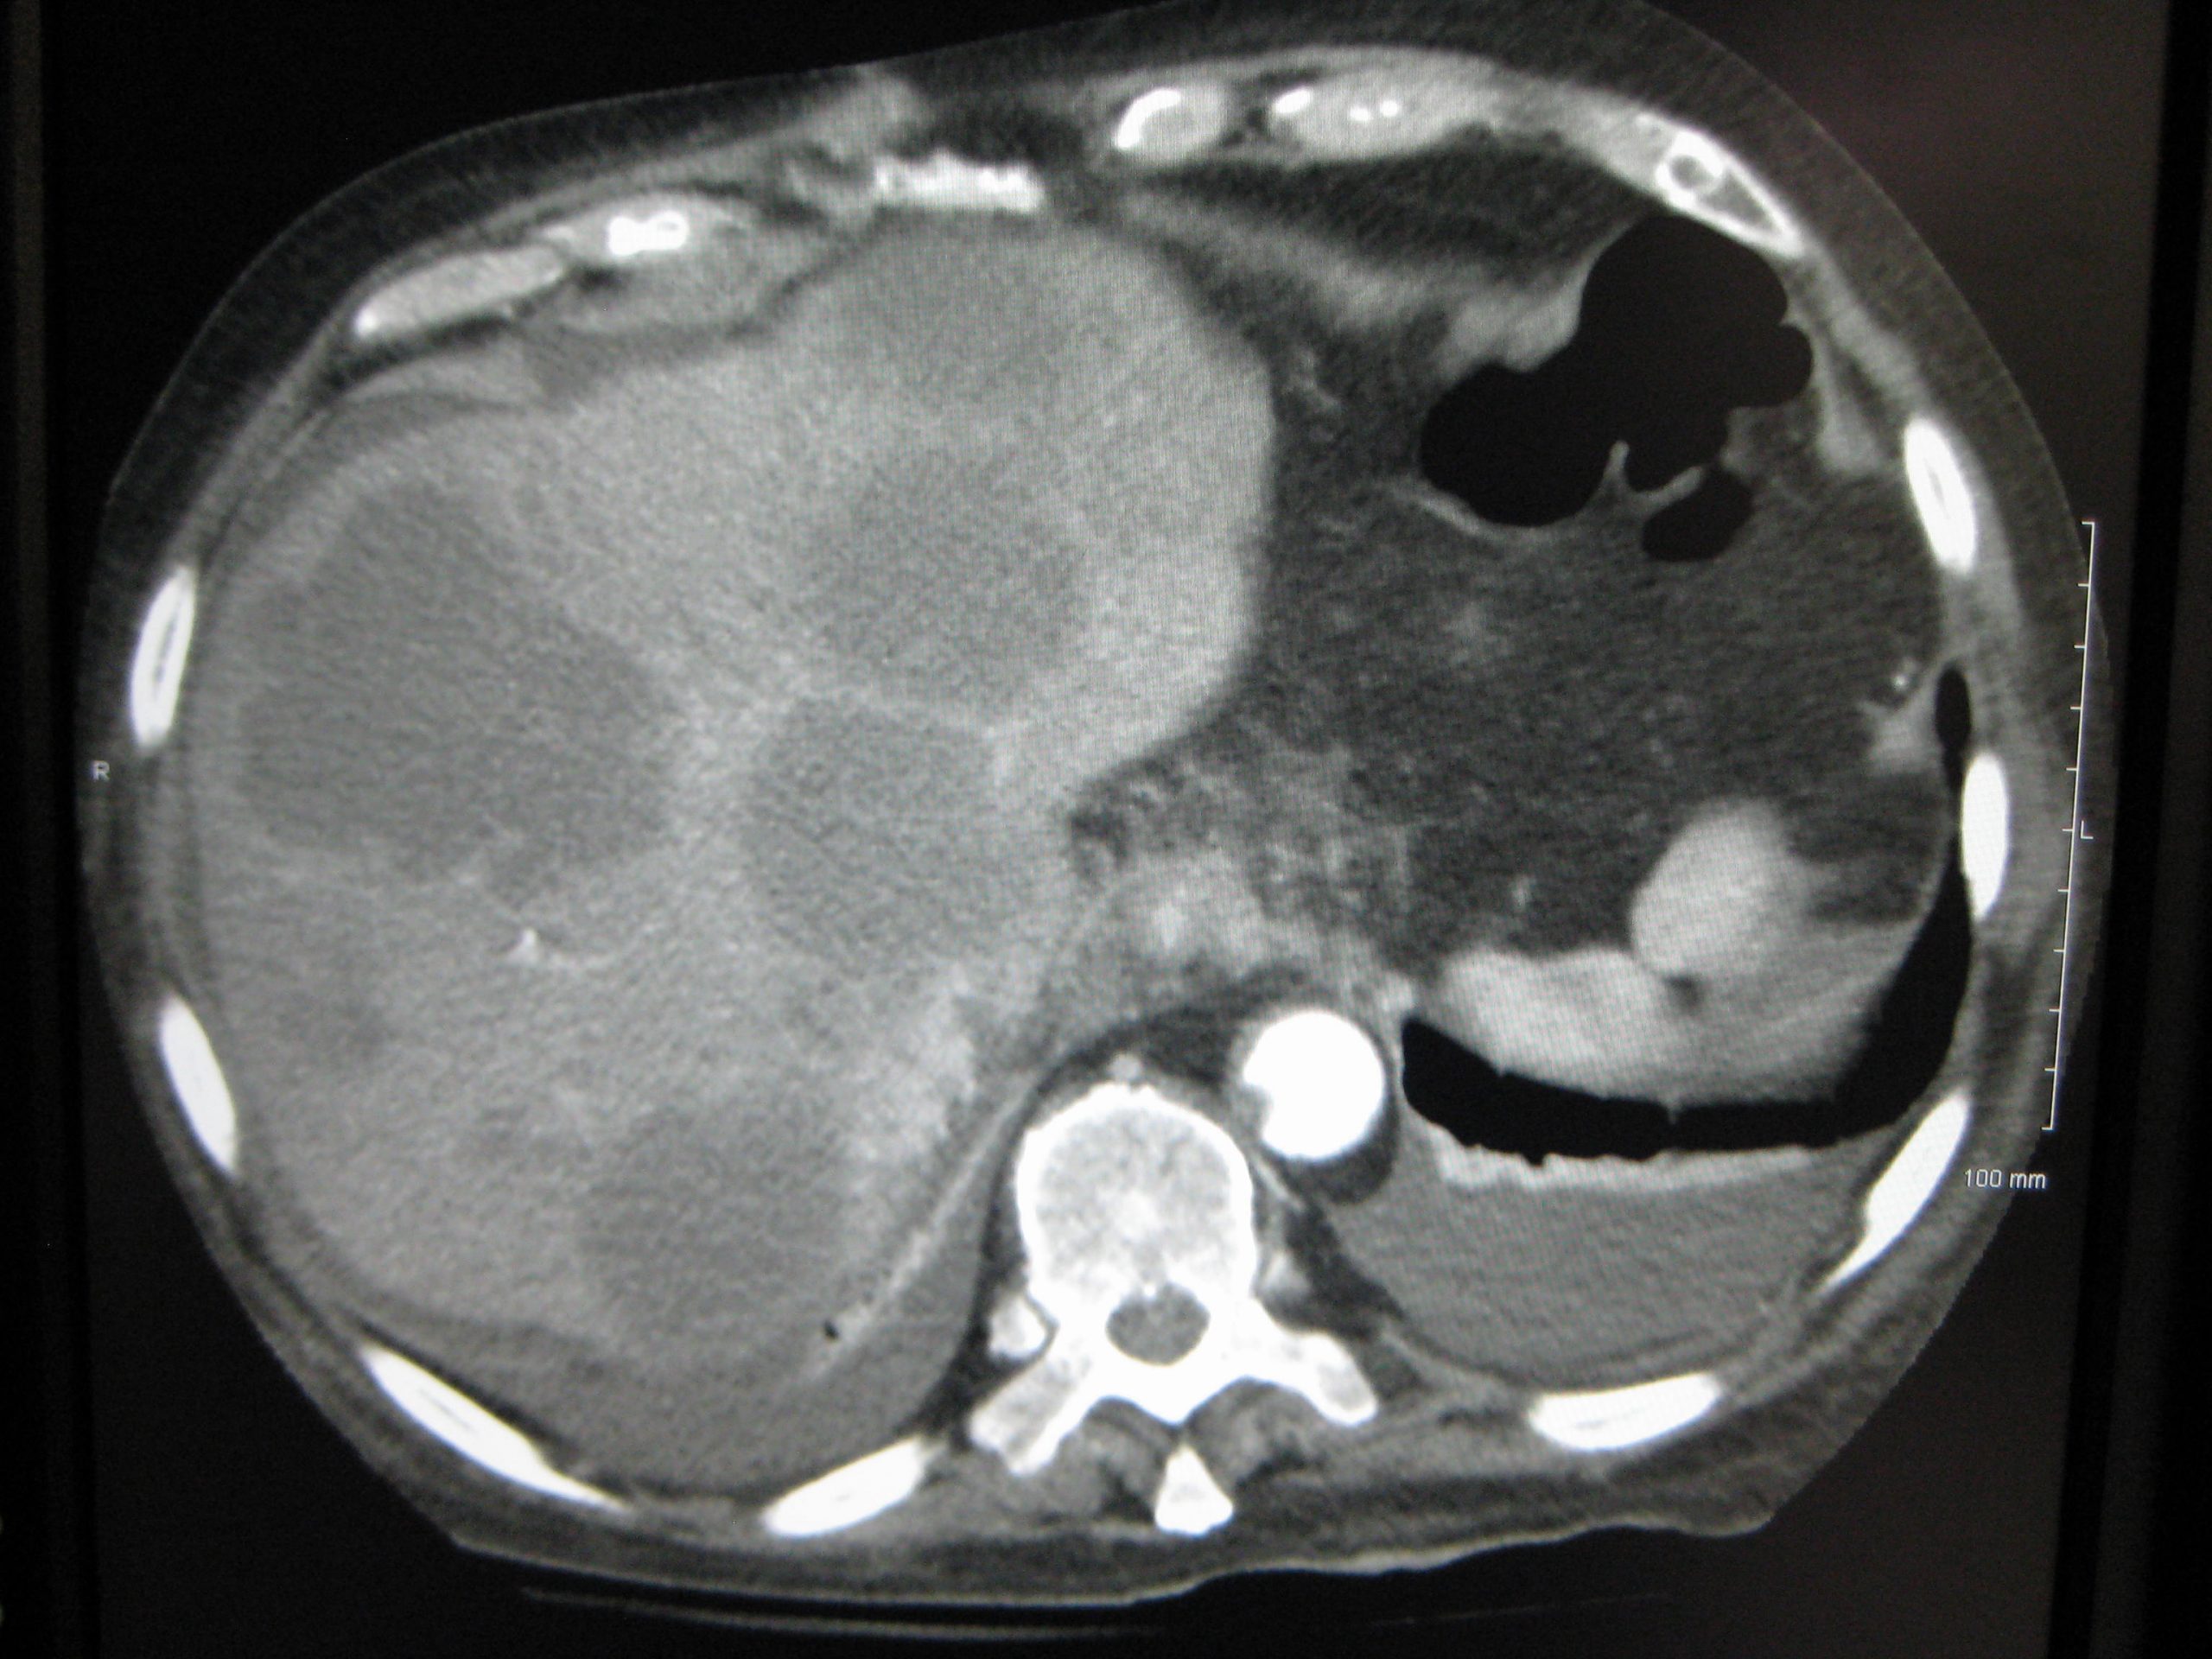

Οι κακοήθεις βλάβες του ήπατος αντλούν το μεγαλύτερο μέρος της παροχής αίματος τους από την ηπατική αρτηρία, σε αντίθεση με τα φυσιολογικά ηπατοκύτταρα που αιματώνονται από την πυλαία φλέβα.

Μολονότι η εκτομή των μεταστάσεων του ήπατος μπορεί να έχει μακροχρόνια επιβίωση σε επιλεγμένους ασθενείς με μονήρεις μεταστάσεις ήπατος, οι περισσότεροι ασθενείς αναπτύσσουν υποτροπιάζουσα νόσο στο ήπαρ μετά την εκτομή.